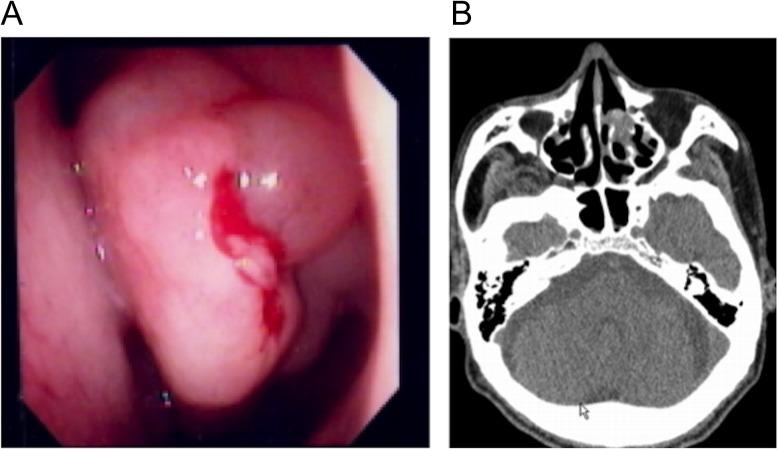

An 84-year-old man visited our hospital with a prolonged productive cough. Chest computed tomography showed a thick wall cavity and bilateral consolidations. Laboratory findings revealed peripheral blood eosinophilia, increased total IgE and elevated myeloperoxidase anti-neutrophil cytoplasmic antibody. Specific IgE and IgG antibodies and an immediate skin reaction against showed positive results. The histological findings of the lung parenchyma were compatible with eosinophilic pneumonia and bronchial biopsy showed eosinophilic vasculitis. Bronchoalveolar lavage fluid culture yielded . These results met the diagnosis criteria for both allergic bronchopulmonary aspergillosis (ABPA) and eosinophilic granulomatosis with polyangiitis (EGPA). This case thus suggests that might be a pathogen common to both diseases, and prolonged exposure to in some patients with ABPA may promote progression to EGPA.

一名84岁男性因长期咳痰前来我院就诊。胸部计算机断层扫描显示有厚壁空洞和双侧实变。实验室检查结果显示外周血嗜酸性粒细胞增多、总IgE升高以及髓过氧化物酶抗中性粒细胞胞浆抗体升高。针对特定物质的特异性IgE和IgG抗体以及即刻皮肤反应呈阳性结果。肺实质的组织学检查结果符合嗜酸性粒细胞性肺炎,支气管活检显示嗜酸性血管炎。支气管肺泡灌洗 fluid culture yielded(此处原文有误,无法准确翻译)。这些结果符合变应性支气管肺曲霉病(ABPA)和嗜酸性肉芽肿性多血管炎(EGPA)的诊断标准。因此,该病例提示某种物质(此处原文有误,无法准确翻译)可能是这两种疾病的共同病原体,并且在一些ABPA患者中长时间接触该物质可能会促进疾病进展为EGPA。